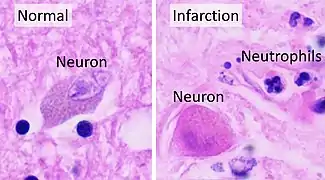

An autopsy of stroke may be able to establish the time taken from the onset of cerebral infarction to the time of death.

Various microscopic findings are present at times from infarction as follows:[25]

| Eosinophilic (red) neurons | 1–35 days |

| Polymorphonuclear leukocytes | 1–37 days |

| Other acute neuronal injuries | 1–60 days |

| Coagulative necrosis | 1 day - 5 years |

| Spongiosis of surrounding tissue | 1 day and older |

| Astrogliosis (gemistocytes) | 2 days and older |

| Neo-vascularization | 3 days and older |

| Hemosiderin pigment | 3 days and older |

| Mononuclear inflammatory cells | 3 days–50 years |

| Macrophages | 3 days–50 years |

| Cavitation | 12 days or older |